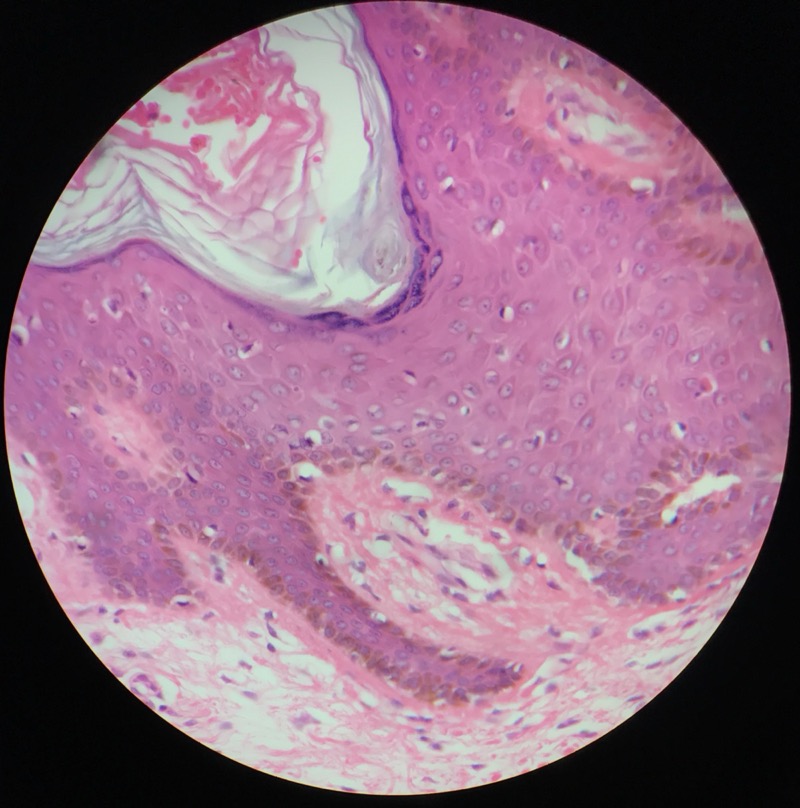

| 1:5:6 | Nagel | ![]() ![]() ![]() ![]() ![]() |